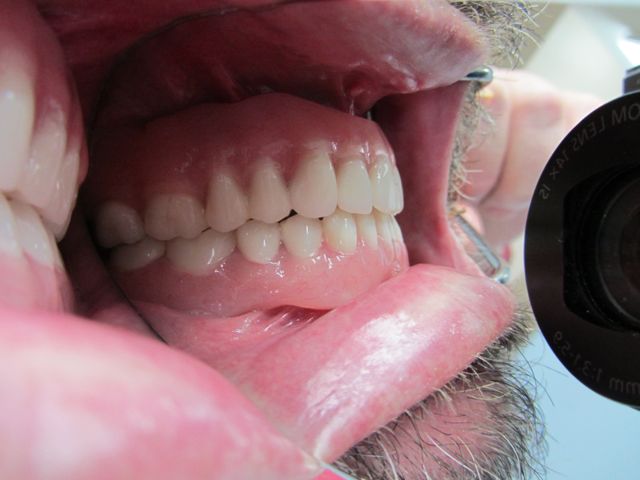

Photo from the side showing how the upper and lower teeth engage. Everything looks ideal.